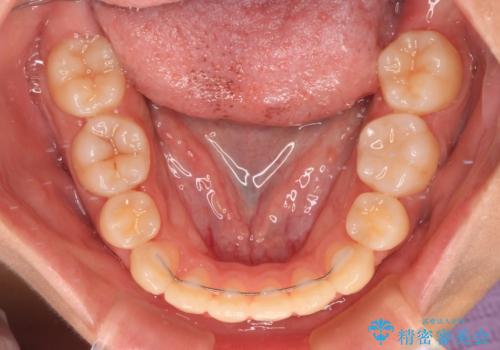

- 抜歯矯正の後戻りを気にして来院された患者様です。

舌の突出癖によるオープンバイトになっていたため、インビザラインによるマウスピース矯正をおすすめしましたが、自己管理の自信がないとのことで、ワイヤー装置による矯正治療を行うこととしました。

舌の突出癖が認められると、上下前歯の隙間を閉じることができません。

舌のトレーニングをしっかりと行っていただくことで、歯列を整えることができます。

- 矯正治療後の保定が不十分だと後戻り(元の位置に戻ろうとする動き)をします